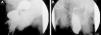

Caso clínicoVarón de 70 años de edad con antecedentes de hipertrofia prostática de 10 años de evolución en tratamiento con tamsulosina, que acude a nuestra consulta por una hernia inguinoescrotal derecha, tras estudio por el Servicio de Urología. Aporta una cistografía en la que se aprecia una herniación del 95% de la vejiga (fig. 1). El paciente refiere la necesidad de comprimir manualmente la hernia para completar la micción. En la exploración física existía una hernia inguinoescrotal derecha que no se reducía en su totalidad.

La cistografía es la prueba de elección para el diagnóstico de las hernias vesicales. Está indicada en varones con hernias inguinoescrotales y enfermedad obstructiva del tracto urinario inferior. La urografía intravenosa, la ecografía y la tomografía computarizada pueden ser útiles en casos asociados a patología del tracto urinario8,11.